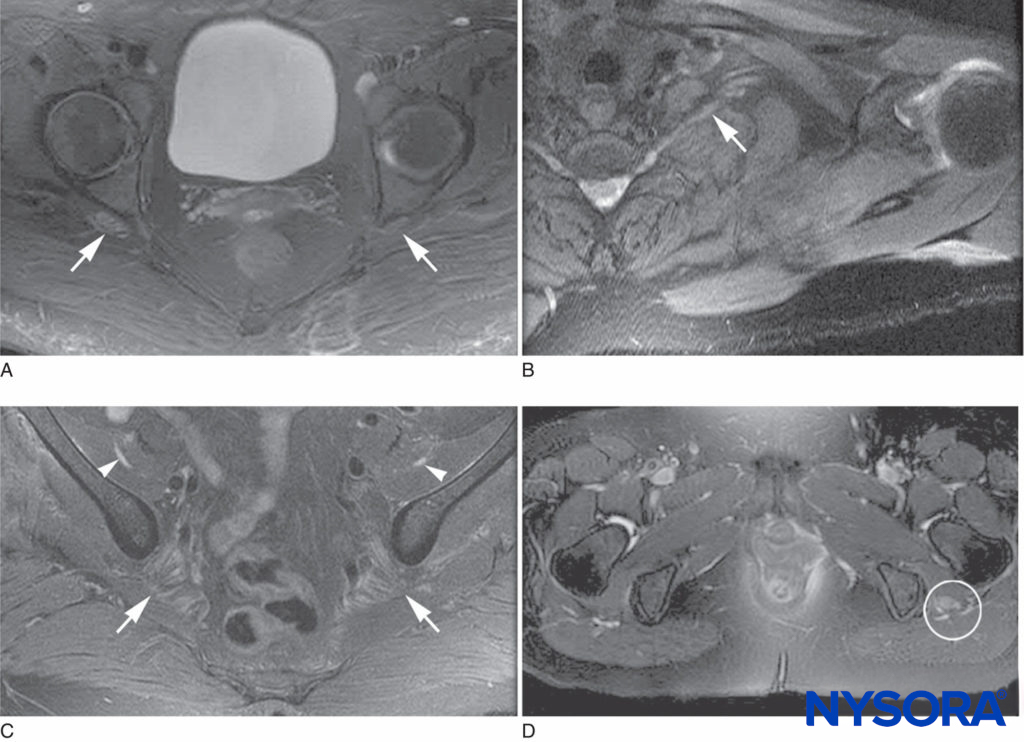

FIGURE 2. Magnetic resonance imaging characteristics of postsurgical inflammatory neuropathy. A: T2 hyperintensity and mild enlargement of bilateral sciatic nerves, right more than left (arrows). B: T2 hyperintensity and mild enlargement of left C8 root and lower trunk (arrow). C: T2 hyperintensity and moderate enlargement of the bilateral femoral nerves (arrowheads) and mild enlargement of the sciatic nerves (arrows). D: T2 hyperintensity and severe enlargement of left sciatic nerve (circled).